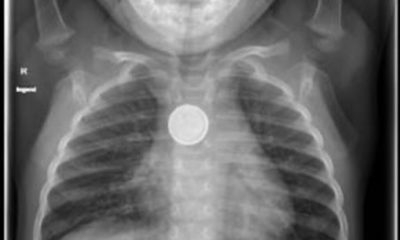

Les pédiatres lancent une mise en garde contre les piles bouton qui mettent en danger la vie des enfants qui en avalent. Le nombre de cas...